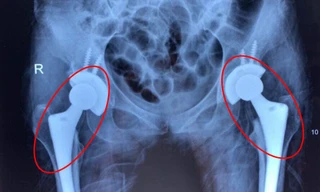

TPO - Tắc mạch máu diễn tiến âm thầm khiến nhiều bệnh nhân bị mục cả 2 khớp háng, đối mặt nguy cơ tàn phế. Bác sĩ cảnh báo, nguyên nhân dẫn tới tình trạng trên là do người bệnh lạm dụng rượu bia. Giải pháp để cứu bệnh nhân là thay cả 2 khớp háng.

Từ nay đến hết tháng 3/2023 Viện Chấn thương chỉnh hình, Bệnh viện Quân y 175 sẽ phối hợp với Tổ chức Operation Walk Chicago (OWC), Hoa Kỳ phẫu thuật miễn phí thay khớp háng cho các bệnh nhân có hoàn cảnh khó khăn.